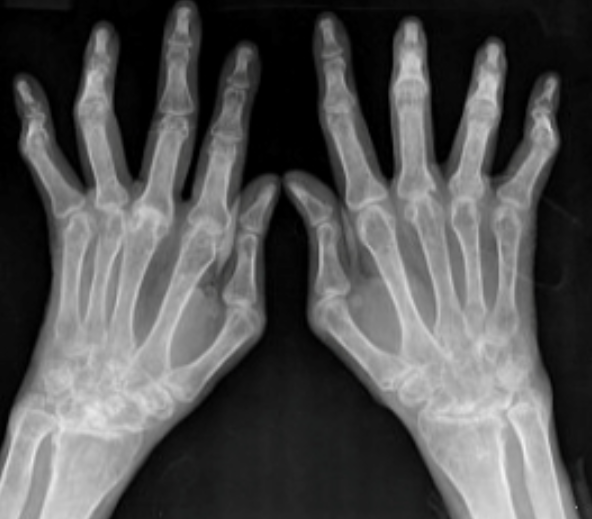

퇴행성 관절염

손가락 마디 통증 원인의 대표적인 케이스입니다.

관절을 보호하고 있는 연골의 손상 또는 퇴행성 변화에 따라 관절 이루는 뼈와 인대 등에 손상이 일어나서 발생합니다. 류마티스 관절염과는 달리 밤에 통증이 심해지는 특성이 있습니다. 초기에는 휴식, 약물 관리 등으로 치료가 가능하나 심해지는 경우 수술이 필요하기도 해서 초기에 확인하는 것이 가장 중요하다고 할 수 있습니다.